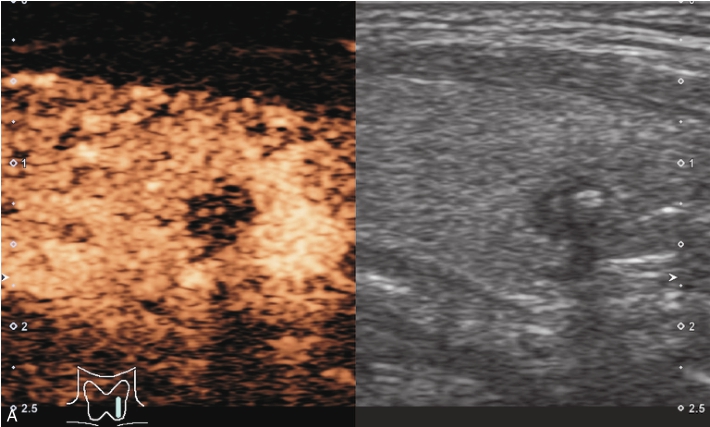

注入造影剂后结节始终呈无增强,边界清晰,周围腺体呈均匀等增强,见图1-3-2、ER1-3-1。

(1)结节内部始终无造影剂灌注,表现为边界清晰、形态规则的无增强区。

(2)结节周边被膜连续完整。

(3)超声造影可以鉴别单纯囊肿与内部为极低回声的甲状腺实性结节,单纯囊肿造影时内部始终呈无增强,边界清,实性结节在造影过程中可见造影剂灌注,边界不清。

图1-3-2 甲状腺单纯囊肿超声造影图

A.注入造影剂后10s;B.腺体增强达峰时(15s)图像;C.注入造影剂后19s,结节内部始终呈无增强